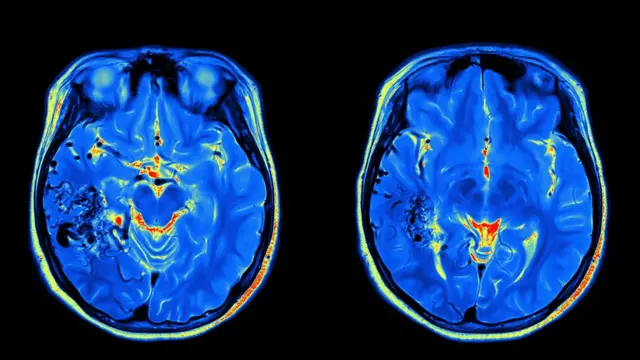

Eso fue lo que determinó un estudio de neurociencia basado en un escáner de cerebro de Sting, el exbajista del popular conjunto británico The Police y ahora solista.

La investigación, cuyos resultados se publicaron en la revista especializada Neurocase, utilizó tecnología de punta para el análisis de imágenes que permitieron abrir una ventana a la mente del virtuoso músico.

"Estas técnicas de punta realmente nos permitieron elaborar mapas de cómo el cerebro de Sting organiza la música", expresó el principal autor del estudio, Daniel Levitin, un psicólogo cognitivo de la Universidad McGill, en Montreal, Canadá.

Tiempo después, Levitin trabajó con Scott Grafton, un experto en escáneres del cerebro de la Universidad de Santa Barbara, California, para aplicar dos técnicas recientemente desarrolladas para el análisis del escáner.

Las técnicas se conocen como análisis de patrón multivoxel y análisis de disparidad representacional.

Estas les permitieron a los científicos ver qué canciones Sting encontraba similares y cuáles diferentes, no basado en pruebas o cuestionarios sino en las regiones de su cerebro que se activaban.

"Estos métodos tienen la habilidad de probar si los patrones de la actividad cerebral son parecidos cuando hay dos tipos de música similares comparada con la actividad cuando los estilos son diferentes", señaló Grafton.

"Esto es algo que nunca antes se había considerado con las imágenes cerebrales generadas durante experimentos musicales".

Según Levitin, el escáner de Sting indicó varias conexiones entre piezas musicales que el científico conocía bien pero que nunca antes había relacionado: "Libertango" de Piazzolla y "Girl" de The Beatles comprobaron ser dos de las más similares en el cerebro del artista.

Ambas piezas están compuestas en claves menores e incluyen motivos melódicos similares, explica el estudio.

Otros ejemplos que revelaron sus similitudes fueron la propia canción de Sting "Moon over Bourbon Street" y "Green Onions", un clásico de rhythm & blues de Booker T. & the M.G.'s.

En este caso, ambas piezas están en la clave de Fa menor y tienen el mismo ritmo de 132 golpes por minuto, un ritmo de swing.